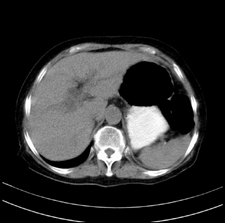

患者,女,75岁。腹痛,体黄5日,膝胸位时腹痛缓解。肝功能明日出来。彩超提示胆总管占位,未见血流信号。心电图提示s-t段改变。患者体质较弱,未能增强。

胆总管上段,腔内有软组织密度影 ,ct值36-44hu。大家看有没有胆管癌的可能。

典型胆总管多发结石;增强扫描前后ct值是否发生改变是鉴别结石与占位的依据。